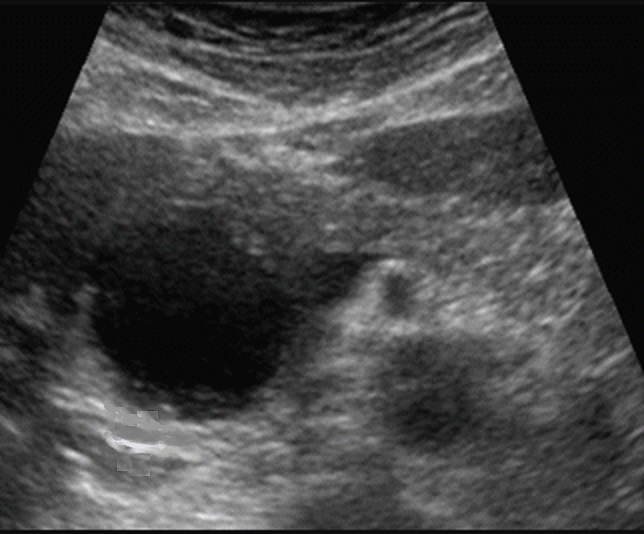

Image

echographique percutane abdominale d'une kyste

hydatique active type I du pancreas avec

aspect lesionnel de nodule ovalaire aechogene a

paroi lisse , bord nette regulier , situe au tete du

pancreas . |

En differencie avec aspect

lesionnel d'echographie d'une pseudokyste du

pancreas aechogene a limite nette regulier et n'a

pas de la paroie . cone de hyper ascoustique

posterique en vue nette |